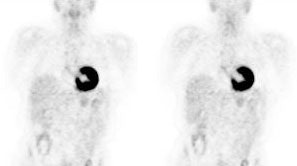

Myocardial activity: Myocardial uptake can be very variable. The patient on the left below had a glucose level of 97 prior to FDG injection. Despite the normal serum glucose, note the intense cardiac activity in this patient. The patient on the right was a diabetic patient with a blood glucose of 169- note that there is no myocardial uptake in this patient despite the elevated glucose level. |

|

|